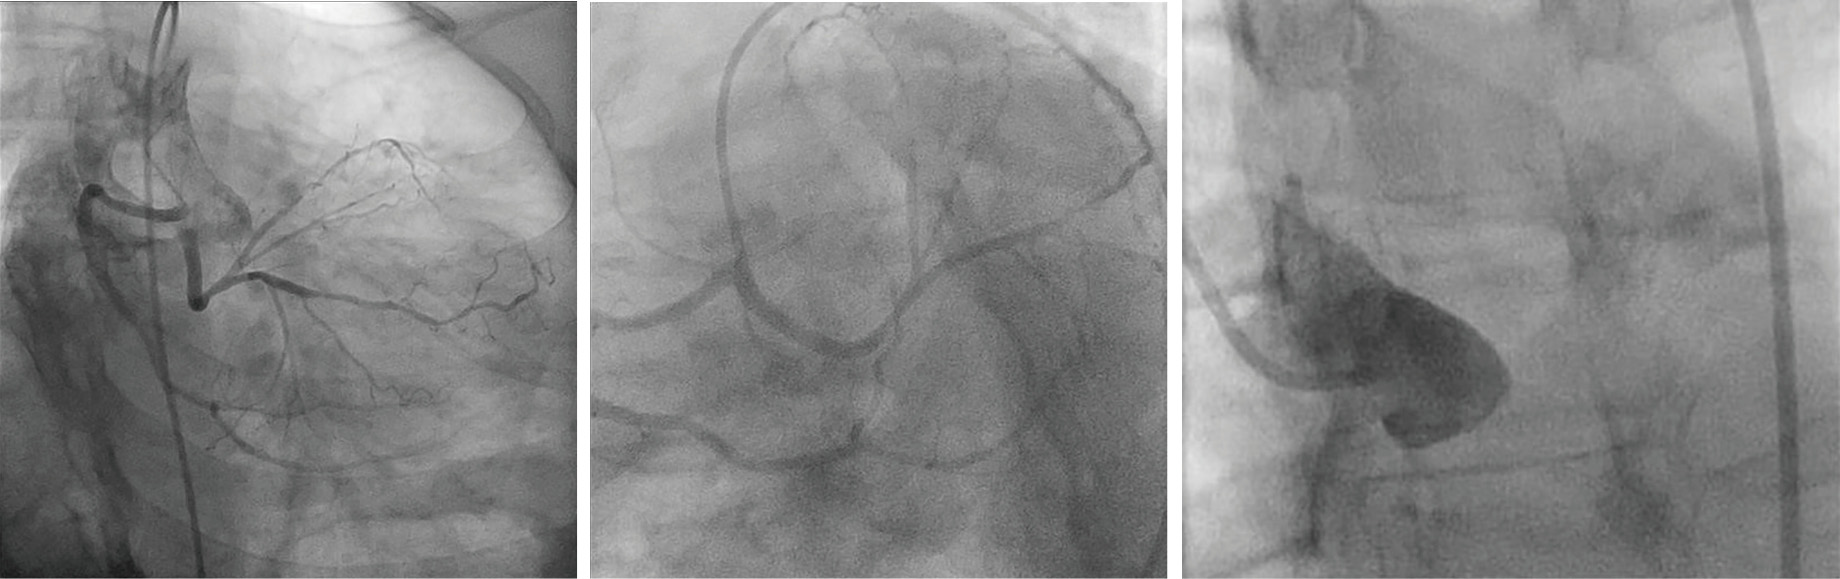

Anomalous origin of the left coronary artery from the right sinus an Journal Of Xiangya Medicine Find the latest published papers in journal of xiangya medicine + top authors, related hot topics, the most cited papers, and related. Published by ame publishing company. Gab1, a therapeutic target for allergic. Journal of xiangya medicine is a journal covering the technologies/fields/categories related to. The journal of xiangya medicine publishes invited articles solicited from recognized experts in their fields. Journal Of Xiangya Medicine.